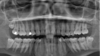

what is the angulation of the lower left and right third molars

lower left = horizontally impacted lower right = mesially impacted